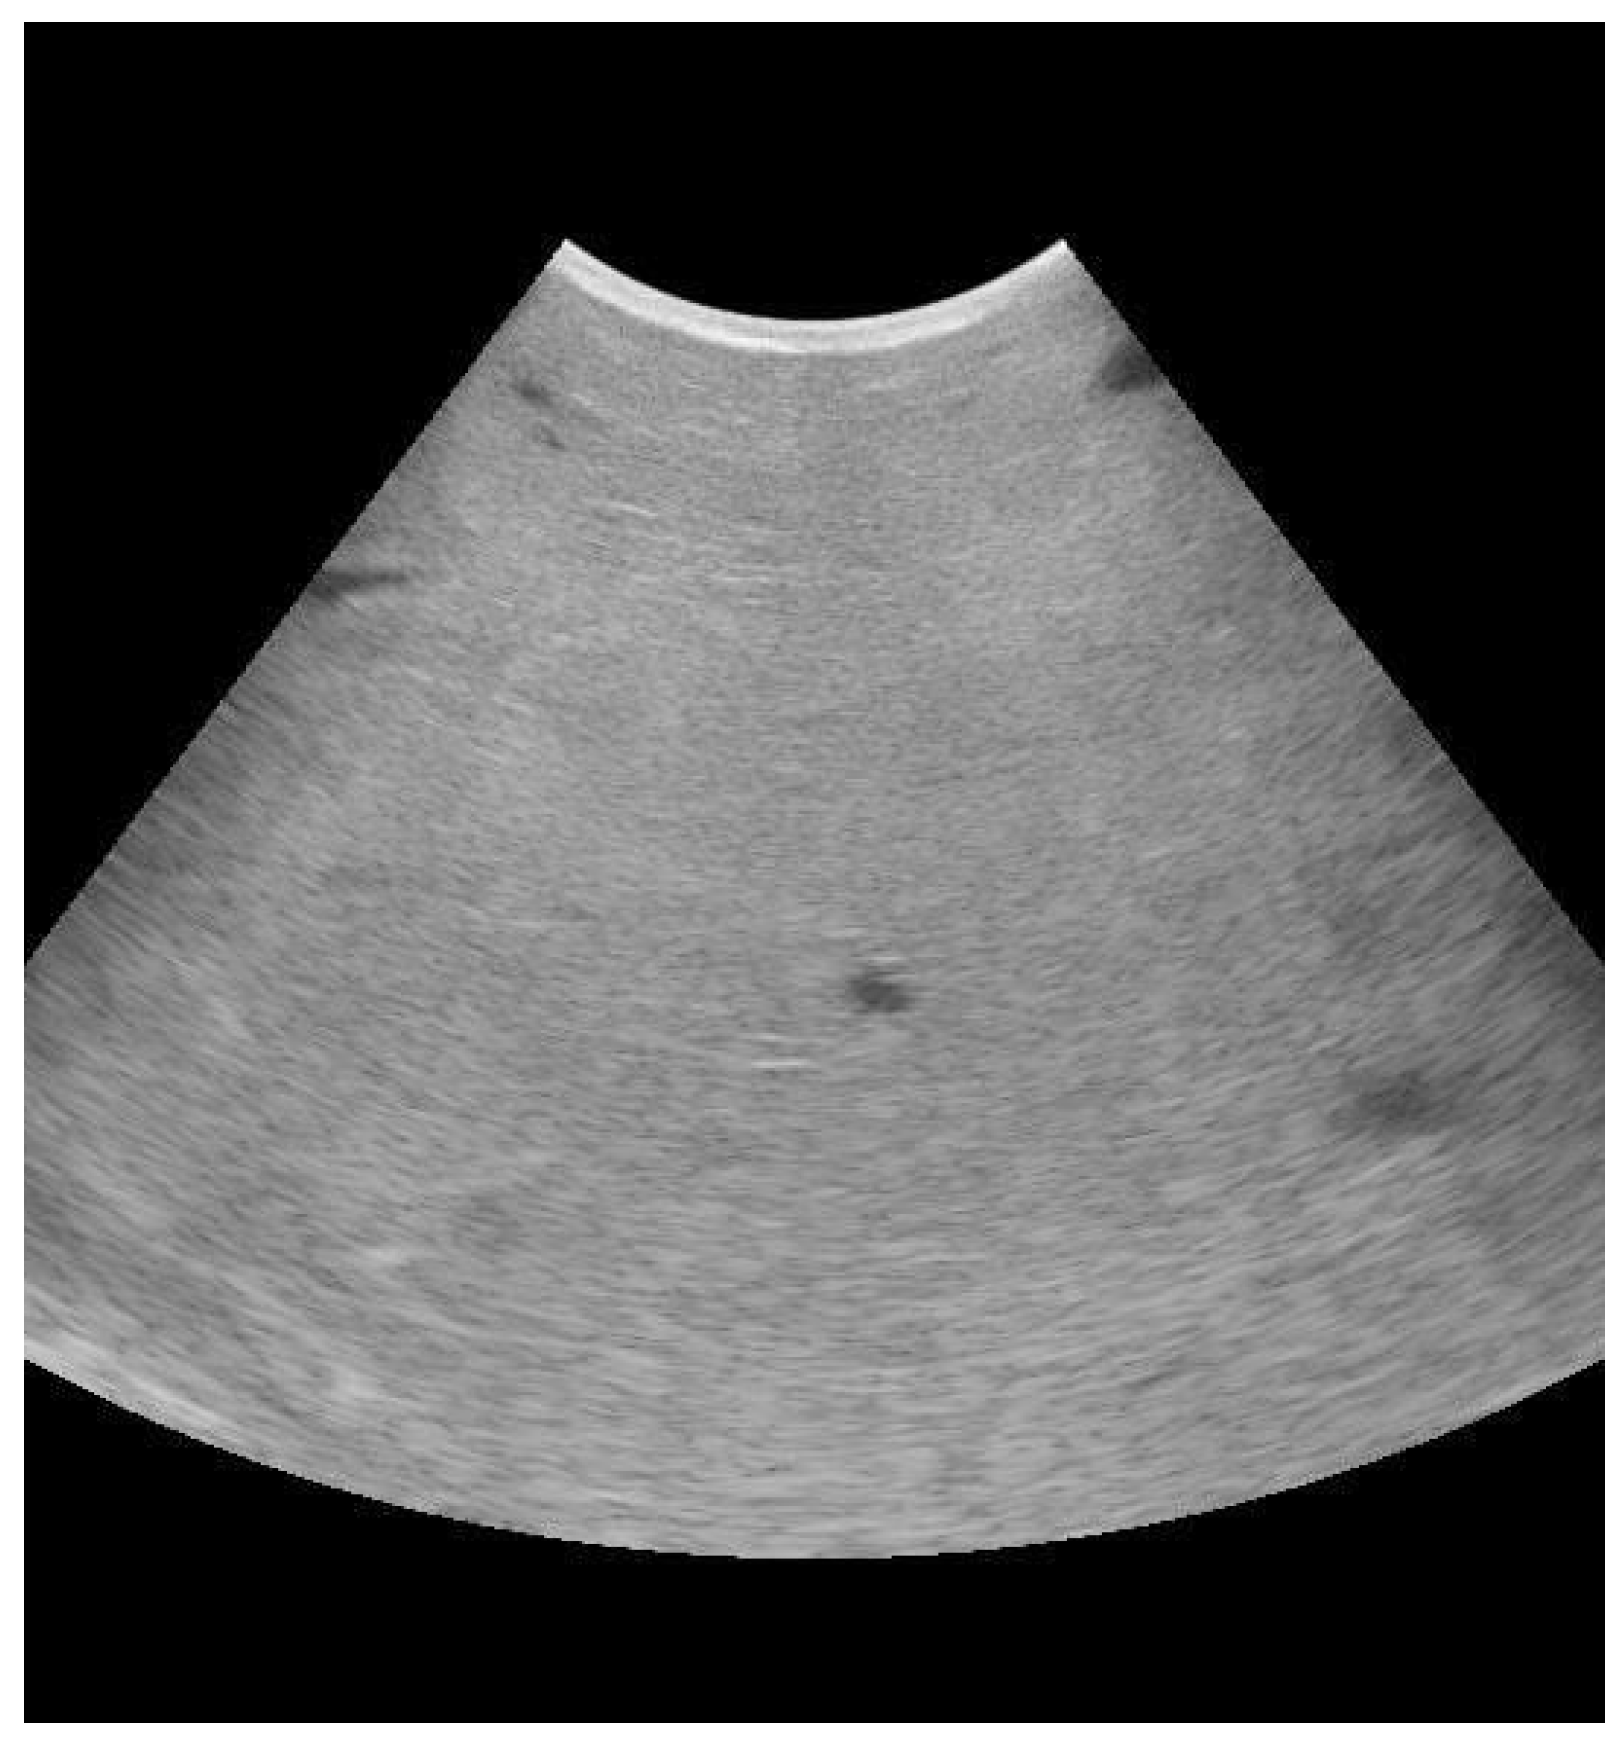

- Suzuki, N.; Kurose, T.; Kaneko, S.; Haraguchi, A.; Isobe, N. Outcome Prediction from the First Examination in Clinical Mastitis Using Ultrasonography in Dairy Cows. Anim. Sci. J. 2020, 91, e13452. [Google Scholar] [CrossRef] [PubMed]

- Flöck, M.; Winter, P. Diagnostic Ultrasonography in Cattle with Diseases of the Mammary Gland. Vet. J. 2006, 171, 314–321. [Google Scholar] [CrossRef]

- Mourya, A.; Shukla, P.C.; Gupta, D.K.; Sharma, R.K.; Nayak, A.; Tiwari, A.; Singh, B.; Singh, A.P.; Sahi, A.; Jain, A. Ultrasonographic Alteration in Subclinical Mastitis in Cows. J. Entomol. Zool. Stud. 2020, 8, 2058–2063. [Google Scholar]